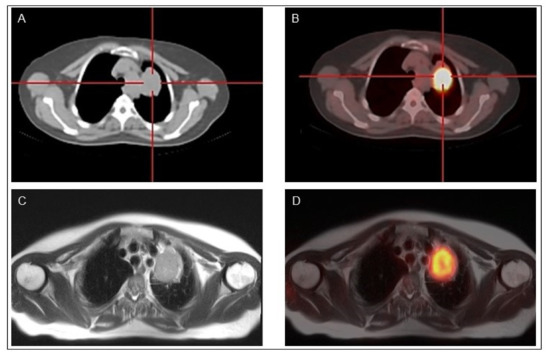

Figure 3.

A 76-year-old patient with prostate cancer and a right thyroid nodule of 15 mm in diameter. Multiple image projections (A), fusion PET-CT images (B), CT images (C) and PET images (D), respectively, of 68Ga-PSMA imaging with high-intensity PSMA accumulation. Fine needle aspiration biopsy of PSMA-avid thyroid lesion was performed revealing an indeterminate cytology. Final histology revealed papillary thyroid cancer.

Indeed, PET/MR when available might be performed in selected patients with bone, soft tissue or liver lesions for whom a MR imaging is indicated (Figure 4).

Figure 4.

Classical papillary thyroid cancer in a 45-year-old man18F-FDG PET-CT (A,B) and 18F-FDG PET-MR (C,D) show a mediastinal lymph node with high 18F-FDG uptake.